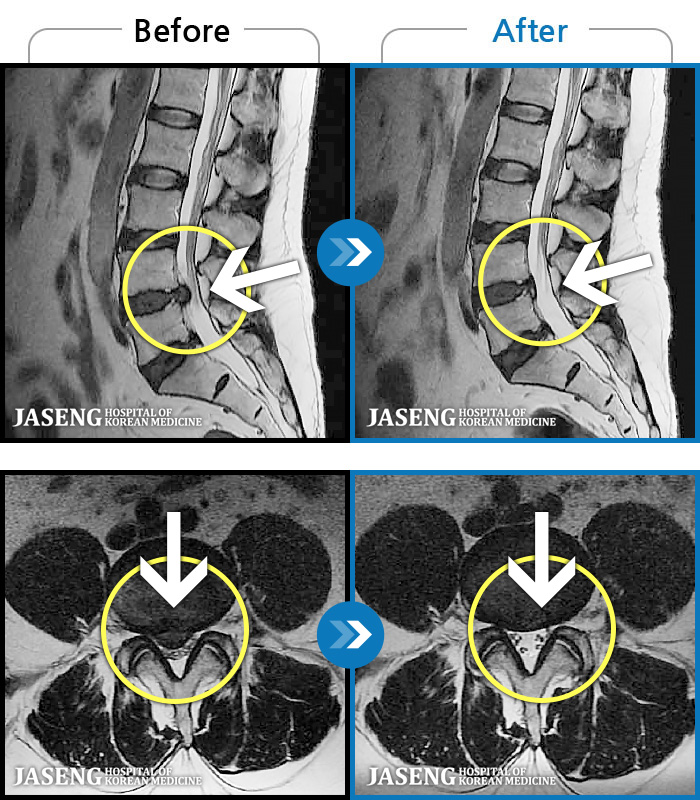

처음 내원 시 허리와 좌측 골반이 많이 아프고, 좌측 다리로 저림과 감각 저하가 있어서 보행이 원활하지 못했으며, 야간통으로 잠도 못 자고 통증 심하여 정상적인 활동이 힘든 상태셨습니다.

2023.09.16 ~ 2024.09.24